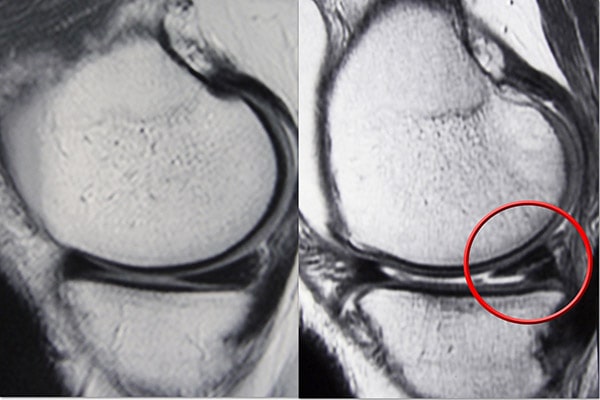

磁共振成像 (MRI) 掃描。 MRI 掃描可評(píng)估膝關(guān)節(jié)的軟組織,包括半月板、軟骨、肌腱和韌帶。